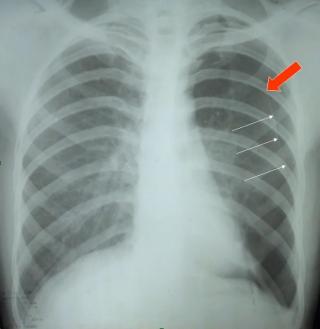

Плоскоклеточный рак представляет собой злокачественную опухоль, которая развивается из плоского эпителия и при этом сохраняет способность к кератинизации в различной степени, поэтому клинические проявления и темпы прогрессирования заметно зависят от органа-источника, глубины инвазии и биологических свойств опухолевых клеток.